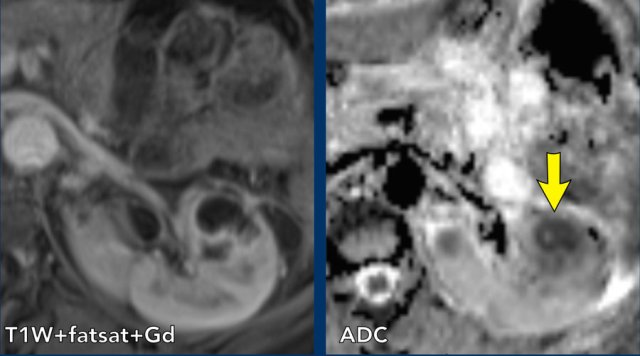

case 3

There is a non-enhancing area in the left kidney on the T1W-image.

This area has low values in the ADC map in keeping with diffusion restriction.

This proved to be an abscess.